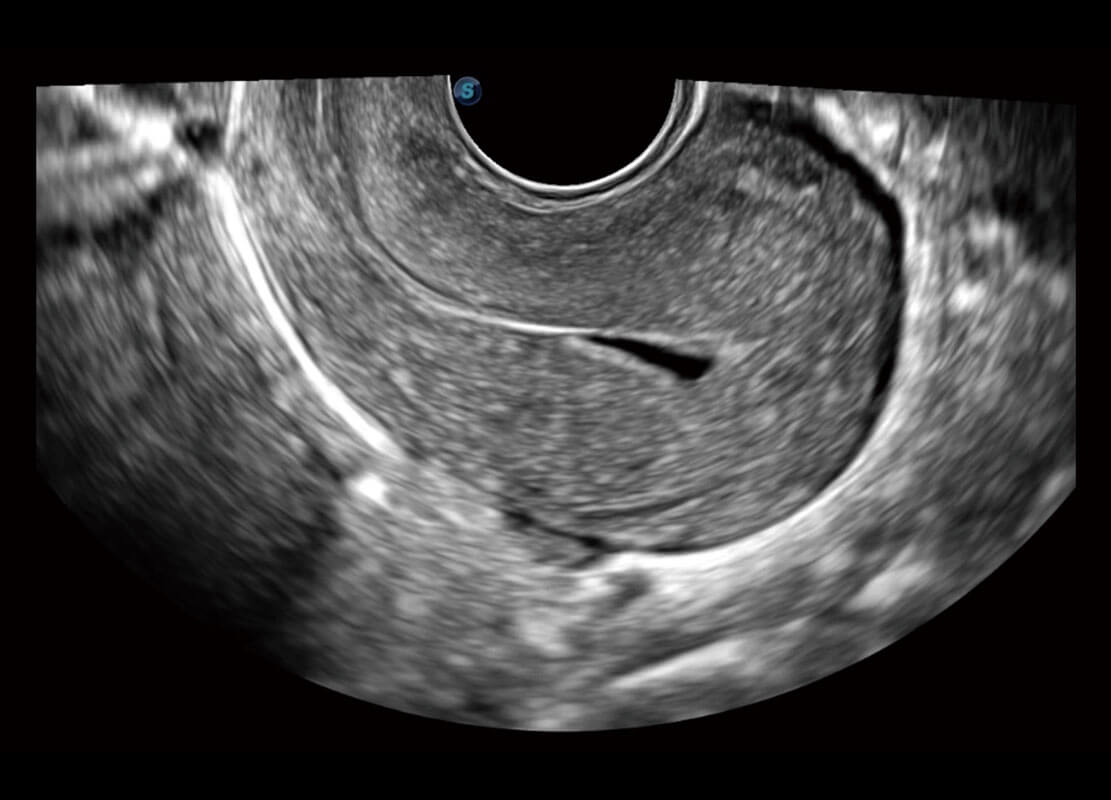

生殖健康

P60优异的图像质量搭载专科探头,在妇科基础疾病的诊断、卵泡生长的监测、输卵管通畅情况的判别等方面为您提供生殖应用方案。

• 腔内三维-宫内节育器

• 腔内三维-光影成像